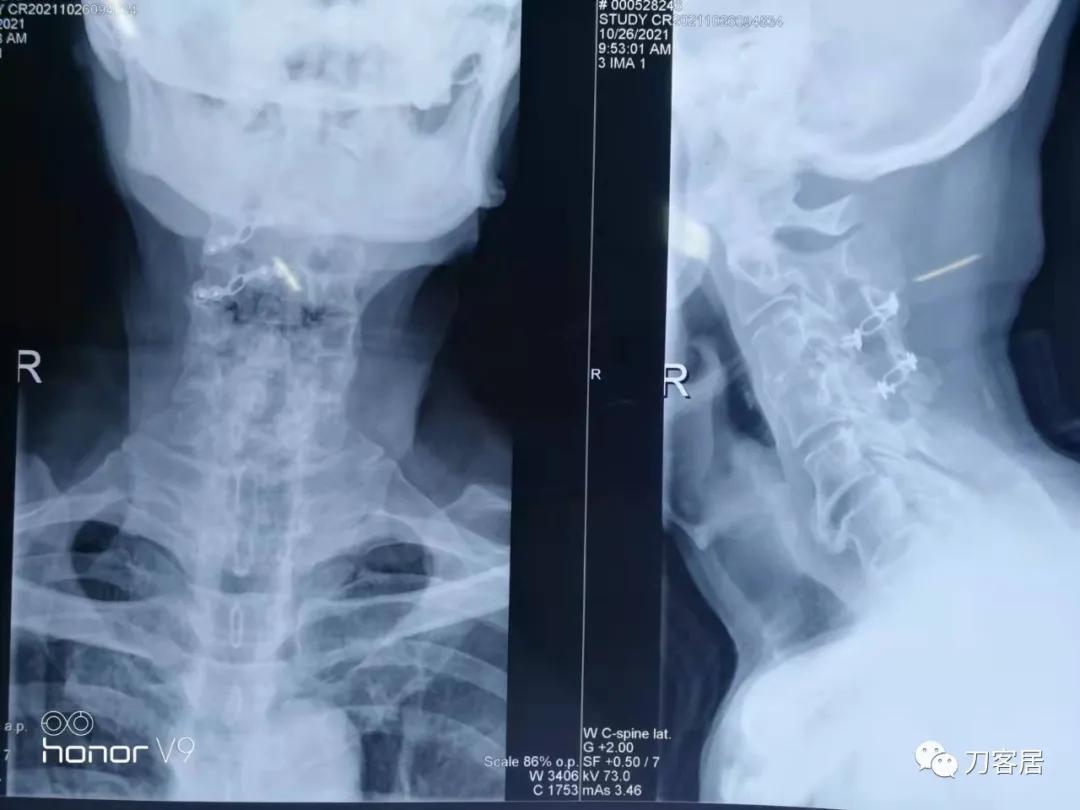

图21. 2021年10月26日颈椎正侧位X线片颈椎椎管成形术后X线片

从这两张颈椎MRI片子来看,颈3-4椎体分节不全,颈2-5椎管成形手术减压很好,椎管无狭窄,脊髓后移,颈5-7椎管有狭窄,脊髓信号改变。此信号改变可能系脊髓萎缩,也可能是头段脊髓后移后,颈5-6节段后方椎板仍在,椎管相对狭窄,脊髓受压。